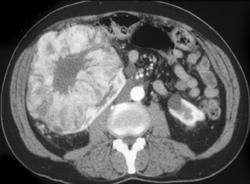

Renal Cell Carcinoma in Dialysis Patient